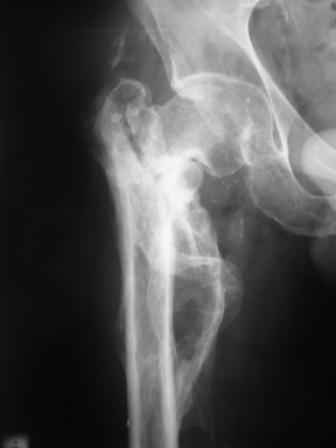

Уважаемый Глеб! Укорочение наверное побольше, да и наружно-ротационная установка скорее всего присутствует. Суставная щель прекрасная, головка живее всех живых. Ратую за подвертельную с латерализацией: исключает нарушение механической оси («исключает вальгус в коленe»), максимально удлиняет без натяжения m.iliacus. Для иллюстрации остеотомия-переделка (слава богу не автопеределка) у мужчины 65 лет.

Филипчук.

PS. Извините за качество последнего снимка, рентгенограмма выполнена по м. жительства, там где был проведен синтез. Последний снимок выполнен через 2 мес. п\о, больной без разрешения начал наступать, слава богу все обошлось.